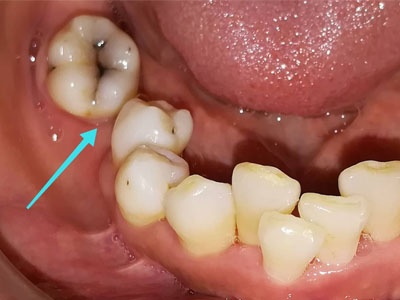

ภาพแสดงช่องว่างจากการถอนฟันกรามและฟันข้างเคียงเริ่มล้มเอียง

เมื่อสูญเสียฟันซี่ใดซี่หนึ่ง จะเป็นฟันกรามใหญ่ ฟันกรามน้อย หรือฟันหน้าก็ตาม ฟันที่อยู่ด้านข้างจะล้มเอียงเข้าหาช่องว่าง ทำให้เกิดฟันห่างในตำแหน่งใกล้เคียง ในขณะที่ฟันคู่สบด้านบนอาจยื่นยาวเข้าหาช่องว่าง ทำให้การสบฟันเปลี่ยนแปลงไป มีจุดสะดุดขณะบดเคี้ยวอาหาร และในระยะยาวฟันที่ล้มเอียงมักจะทำความสะอาดยาก ทำให้มีปัญหาฟันผุและโรคเหงือกอักเสบตามมาได้